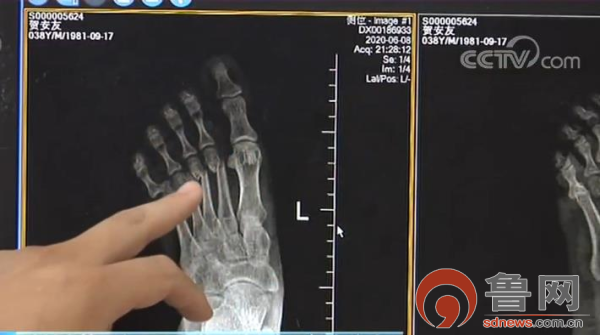

聊城市第三人民医院外一科主治医师赵忠全介绍:“当时来的时候左足肿胀,这是他的片子,左足的第2、3、4跖骨骨折,第6跖趾关节脱位。我们连夜给他开通了绿色通道,准备了急诊手术,现在患者术后恢复良好,切口愈合良好。”